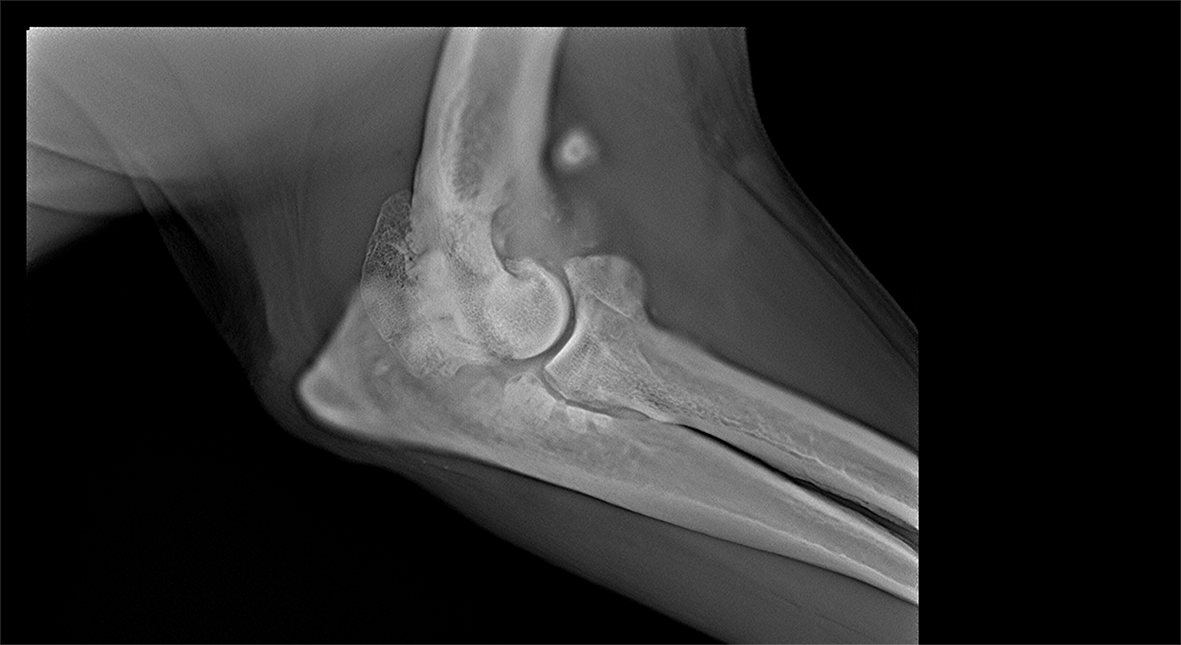

The Adaptix Ortho350 is a cutting-edge, portable Digital Tomosynthesis (DT) system designed to provide high-resolution, low-dose 3D imaging for musculoskeletal diagnostics. This revolutionary system addresses the limitations of traditional 2D X-ray imaging while offering a more accessible, cost-effective alternative to full CT scans.

This advanced hardware innovation enables the rapid acquisition of multiple low-dose X-ray projections from different angles, which are then reconstructed into a highly detailed, depth-resolved 3D image. This allows clinicians to visualise complex bone structures with greater clarity, improving diagnostic accuracy for fractures, joint conditions, and degenerative diseases.

Experience point-of-care 3D imaging that boosts diagnostic confidence with specialized capabilities for weight bearing knee, ankle and foot imaging, as well as detailed upper extremity imaging.